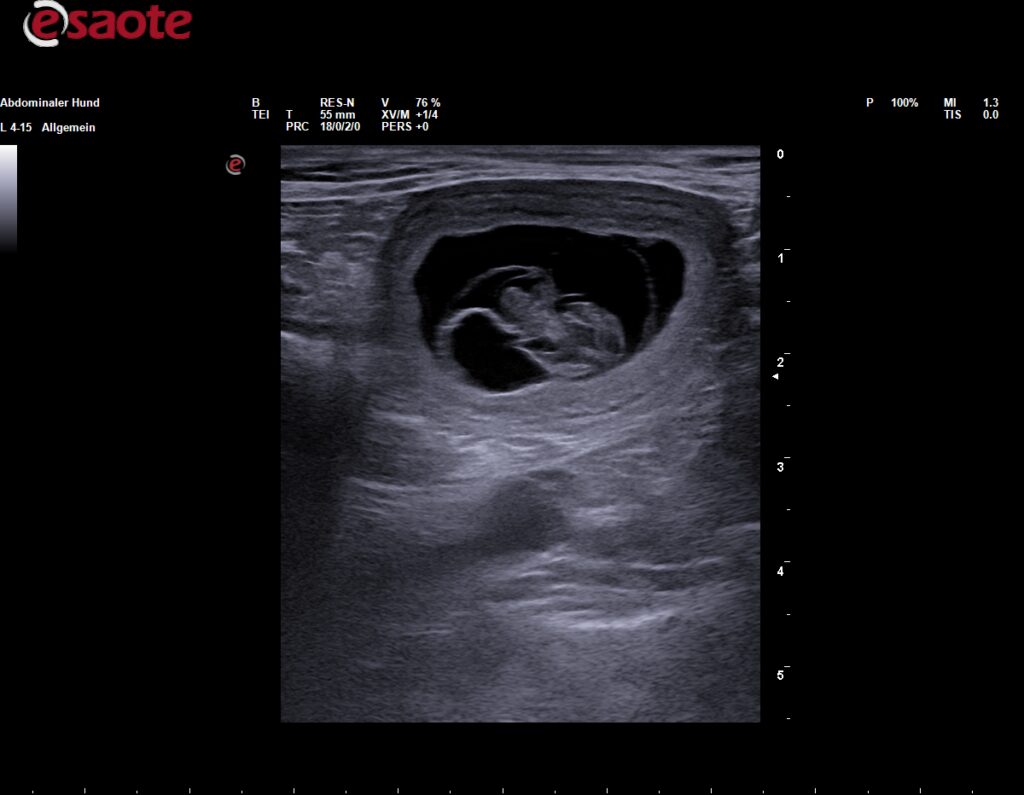

Am 03.09.2025 hat der Ultraschall es bestätigt, Baya ist trächtig! Es wurden mindestens 4 Welpen gesehen, es bleibt spannend. In der ersten Oktoberwoche kommt unser G-Wurf zur Welt.